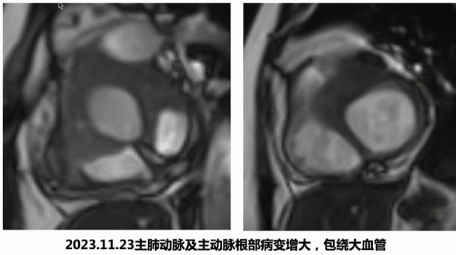

但在2023年11月检查时,发现主肺动脉及主动脉根部病变增大并包绕大血管,2024年3月患者再次住院系统评估,此时实验室检查提示除抗核抗体阳性外,ANCA抗体也呈阳性。

住院期间患者出现平卧时发作性胸痛伴大汗,呈撕裂样,持续十余分钟好转后再发。床旁心电图提示V1导联ST段较基线压低,复查心电图可见广泛胸前导联ST段压低。考虑到主肺动脉周围病变增大,完善冠脉CTA检查,结果显示主动脉根部和肺动脉之间的病变包绕冠状动脉,导致左主干近端闭塞及右冠状动脉近端狭窄,因此判断患者胸痛症状与纵隔占位累及冠脉引起心肌缺血相关。

随即对患者进行冠脉搭桥术及活检术,手术病理提示纵隔占位性质为急慢性炎伴坏死,局灶可见大量淋巴细胞聚集,部分血管周可见炎细胞聚集,结合ANCA阳性及之前鉴别诊断,考虑符合ANCA相关性血管炎,肉芽肿性多血管炎可能性大。后续治疗调整为泼尼松60mg qd联合环磷酰胺及MMF治疗,术后3个月随访显示纵隔病变未复发,垂体病变稳定,无新发临床症状,激素规律减量过程顺利,患者取得较好治疗效果。